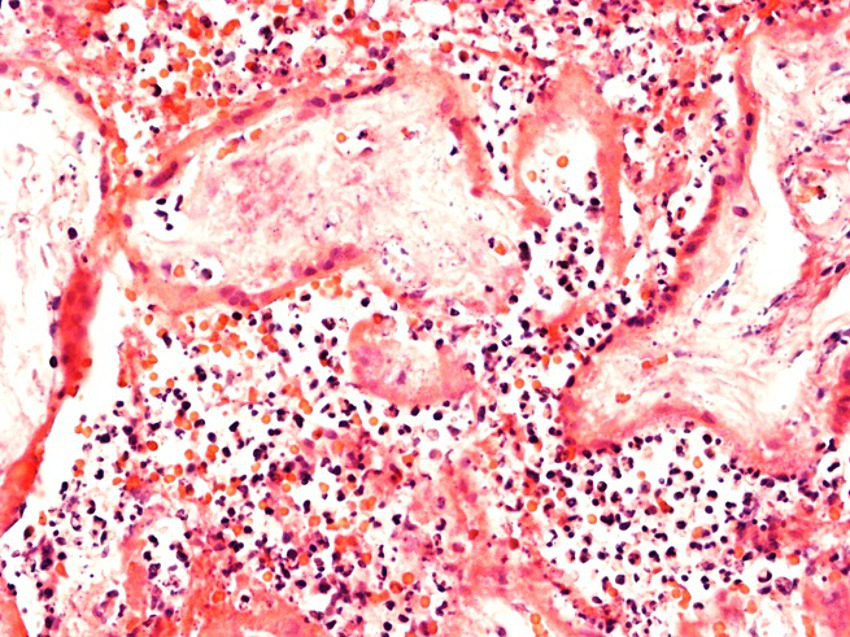

In Case2i (stillbirth at 30 weeks of gestation), placental qPCR was positive for SARS-CoV-2. Pathology showed marked CHI (Table 3; Figure 6), whereas variant sequencing revealed the B.1.617 (Delta) variant. Alltogether, two of the stillbirth cases in the infection group were recruited during Delta, whereas Case3i was recruited during Omicron dominance.

Figure 6

Evidence of marked chronic histiocytic intervillositis. Representative images of case 2i with stillbirth at 30 weeks of gestation.

Placental histopathology for Case1i (miscarriage at 18 weeks of gestation) revealed fulminant villitis and chorioamnionitis with extensive placental infarction and for Case2i massive proliferation of the intervillous fibrin with single intercalated lymphocytes and macrophages (Figures 6, 7).